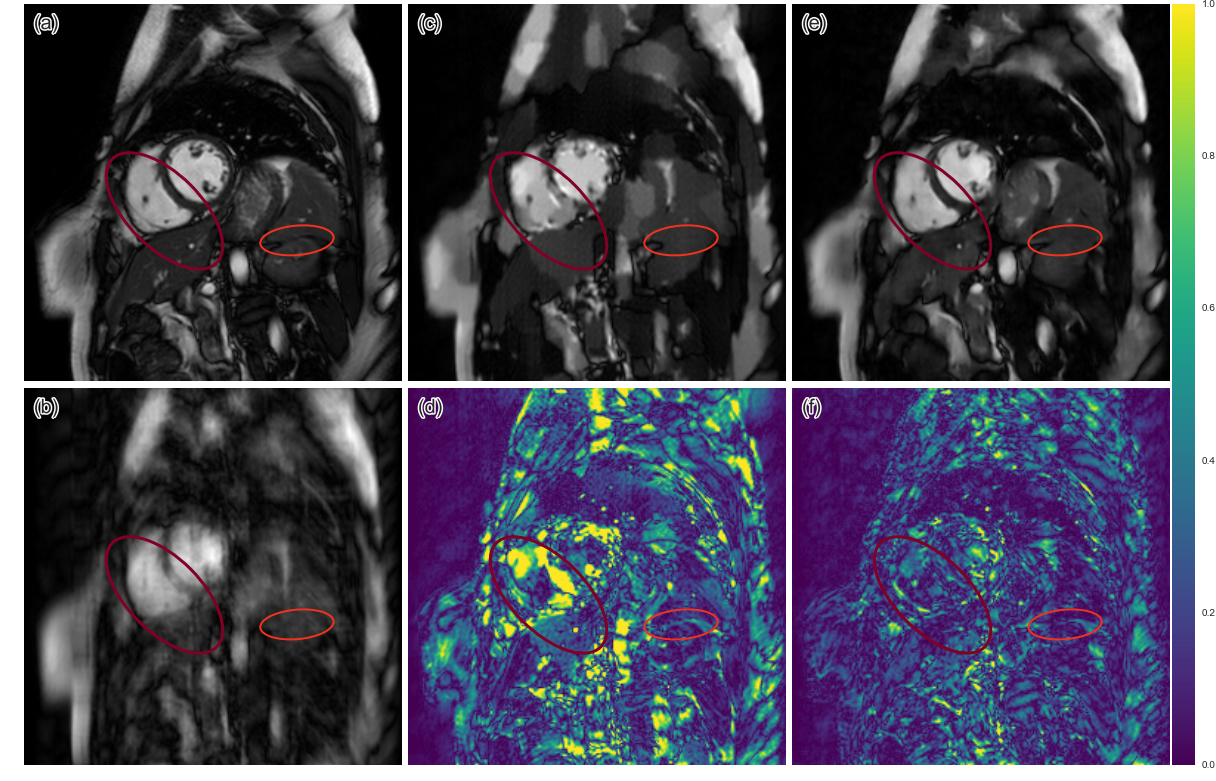

Figure 2: The comparison of reconstruction from DLMRI and CNN. (a) The original, (b) 3x undersampled, (c)-(d) DLMRI reconstruction and its error map ×5absent5\times 5 and (e)-(f) CNN reconstruction and its error map ×5absent5\times 5.

The means of the reconstruction errors across 10 subjects are summarised in table 1. For both 3-fold and 6-fold acceleration, one can see that CNN consistently outperformed DLMRI, and that the standard deviation of the error made by CNN was smaller. The reconstruction from 3-fold acceleration can be found in Figure 2. It can be seen that the CNN approach produced a smaller overall error. The CNN reconstruction produced a more homogeneous reconstruction. On the other hand, DLMRI gave a blocky reconstruction. In some cases, both CNN and DLMRI suffered from small losses of important anatomical structures in their reconstructions (orange), but CNN was able to recover more details (red). The reconstructions from 6-fold acceleration is in Figure 3. Although both methods suffered from significant loss of structures (orange), CNN was still capable of better preserving the texture than DLMRI (red). On the other hand, DLMRI created extremely block-like artefacts due to over-smoothing. 6x undersampling for these images typically approaches the limit of sparsity-based methods, however, CNN was able to predict some anatomical details which was not possible by DLMRI. This could be due to the fact that CNN has more free parameters to tune with, allowing the network to learn complex but more accurate transformations of data.

Figure 3: The comparison of reconstructions from DLMRI and CNN. (a) The original, (b) 6x undersampled, (c)-(d) DLMRI reconstruction and its error map ×5absent5\times 5 and (e)-(f) CNN reconstruction and its error map ×5absent5\times 5.